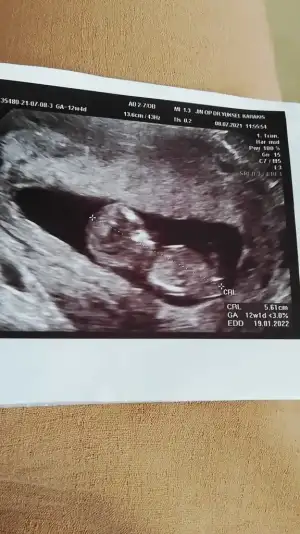

Kız görünüyor11+2 bı tahminde bulunur musun canım Eki Görüntüle 2894305

Kız gibi sanki

11+3 ultrasonuna göre tahmininiz nedir?10 haftaya göre kız ama en iyi 11 12 13 haftalar olmalı tekrar USG paylasin![]()

11+3 e göre tahmininiz nedir?10 haftaya göre kız ama en iyi 11 12 13 haftalar olmalı tekrar USG paylasin![]()

Kız görünüyor